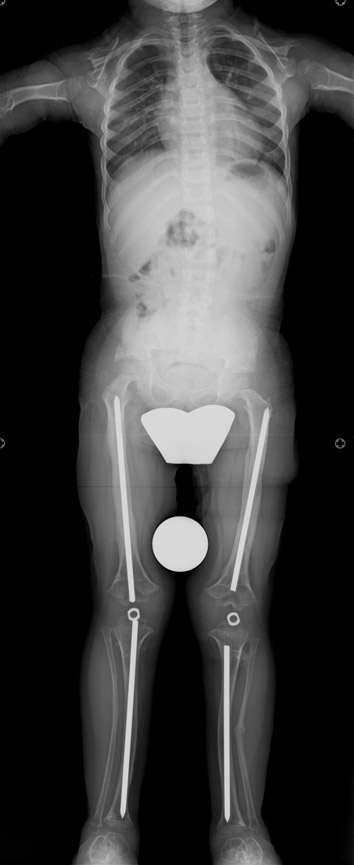

6-8 yaşları arasında Femur (uyluk) ve tibiada (bacak) toplam 10cm boy uzatma (6cm femur ve 4 cm tibia) Parantez bacak deformitesinin düzeltilmesi Ortalama eksternal fiksasyon tedavi süresi = 5 ay İkinci, üçüncü ve dördüncü boy uzatmalar Yetişkin stratejisinde (aşağıda) olduğu gibi Alt uzuvlarda (Diz üstü ve altı dahil) toplam 30-35 cm boy uzatma Üst uzuvlarda toplam 10-12 cm boy uzatma

12-14 yaşları arasında Her iki tibiada toplam 10-15cm boy uzatma (iki seviyeli uzatma) Proksimal tibianın varus deformitesini proksimal osteotomi ile düzeltilmesi Distal tibianın varus deformitesi distal osteotomi ile düzeltmesi Distal tibianın varus deformitesi distal osteotomi ile düzeltmesi Boy uzatmanın sonunda lateral kollateral ligamentin gerilmesi Ortalama eksternal fiksasyon tedavi süresi = 8-10 ay

13-15 yaşlar arasında Her iki humerusu (kol) 8-12 cm boy uzatma Dirseklerin fleksiyon deformitesini düzeltme Ortalama eksternal fiksasyon tedavi süresi = 6-8 ay Alt uzuvların iki uzatması arasında üst uzuvlar uzatılarak alt uzuvların dinlenmesi sağlanmış olur. Cihaz çıkartıldıktan sonra en erken ikinci uzatmaya başlama süresi 6 aydır. Bilateral femoral uzatmalarda uzatma fazı sırasında hastanın yürümesi mümkün değildir. Ayakta durmaya sadece hasta transferi sırasında izin verilir. Uzatma fazında ambulasyona sadece tekerlekli sandalye ile izin verilir. Konsolidasyon fazında ise tedrici olarak daha fazla yük verilmesine ve cihazın çıkmasına yakın serbest yürümeye izin verilir. Bilateral tibial uzatmalarda ilk günden itibaren yürüteç veya koltuk değneği ile hastanın yük vermesine izin verilir. Uzun gezintiler tekerlekli sandalye ile yapılmalıdır. Bilateral humeral uzatmalarda hemen hemen hiçbir aktivite kısıtlaması yoktur. Uzatma süresince her iki haftada bir yapılan takiplerde kantitatif duyusal sinir testleri doktor tarafından yapılmalıdır. Bu gelişmekte olan sinir sorunlarını klinik olarak ortaya çıkmadan yakalamaya izin verir. Femoral ve humeral uzatmalarda çok nadir görülmesine rağmen tedavi edilmedikleri durumda düşük ayağa (ayağı yukarı çeken kasları innerve eden sinirin felci) neden olabilirler. Eğer erken tespit edilir ve uzatmanın hızı azaltılırsa, sinir problemi genellikle kendiliğinden düzelir ve uzatmaya düşük hızda devam edilir. Uzatmada yavaşlamaya rağmen sinir problemi devam ederse sinirin cerrahi olarak gevşetilmesi gerekir. Bu işlem 1cm’ lik bir kesi ile yapılabilen ve hastanede bir gece kalmayı gerektiren küçük bir işlemdir. Bu ameliyat el bileğinde sinir sıkışması (karpal tünel sendromu) için yapılana benzerdir.